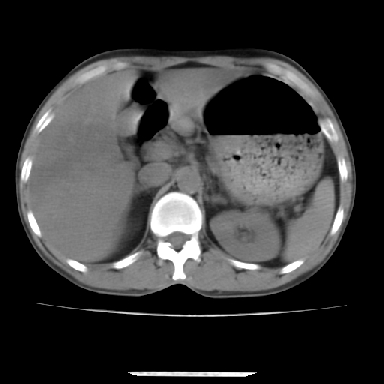

标题: CT7372:脂肪肝?外伤? [打印本页]

标题: CT7372:脂肪肝?外伤?

m 45 车祸,硬膜下血肿

窗宽太宽,调低点就好了,应该是不均质脂肪肝表现,请结合临床,单纯肝挫伤  其内无出血灶很少见,必要时做mri检查

窗宽太大,对比度太差了。局限性脂肪肝也有可能,但是亦不排除外伤性改变,增强扫描应该也还可以鉴别的。

肝内未见出血灶,但不能除外外伤性肝损伤,所示层面应考虑弥漫性脂肪肝.请结合临床必要时做mir检查

肋骨无骨折,腹腔未见游离液体,所以不均匀脂肪肝首先考虑,但如果病人情况允许还是做个增强检查放心

考虑不均匀性脂肪肝,肝包膜下光整,肋骨无异常,无腹水征,不支持肝挫伤。